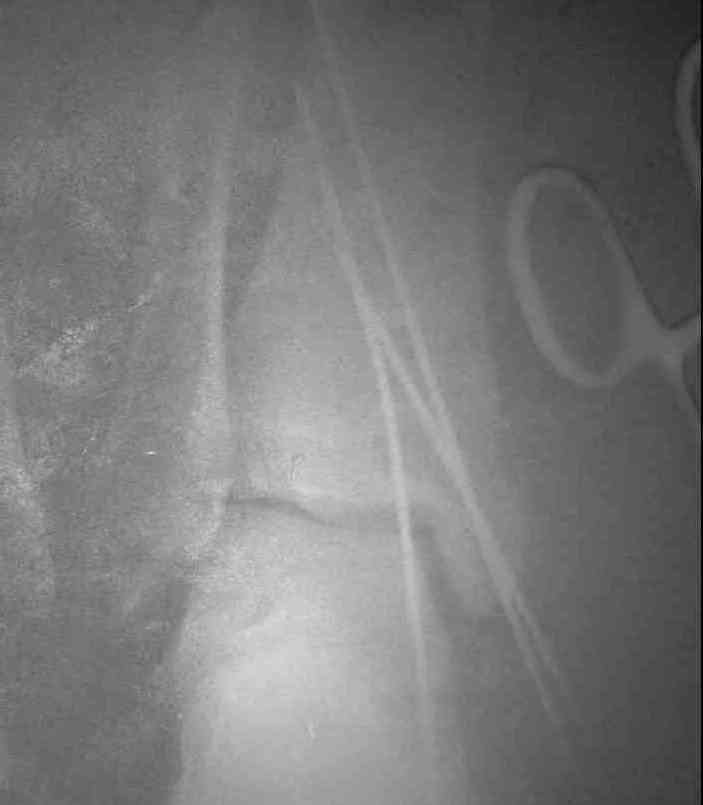

Уважаемые коллеги! Хотел-бы продолжить разговор об исходах переломо-вывихов в голеностопном суставе. При этом, в данном конкретном случае, хотелось узнать мнение опытных коллег об эндопротезировании. На консультацию обратилась пациентка, 26лет. В 2002 году открытый переломо-вывих. Лечение: вправление, трансфиксация спицами и гипсовая повязка. Около 4-х месяцев сохранялись явления нагноения вокруг спиц. На сегодня - движения в суставе отсутствуют, постоянные боли, функциональное укорочение конечности = 3 см. На недавней конференции по хирургии стопы и голеностопного сустава демонстрировался эндопротез НИИТО им. Вредена, внешне понравился. Юрий Алексеевич Булахтин

I would try to convince the p-nt for Arthrodesis providing all the usual things are OK-We see only the X-Rays of the p-nt.